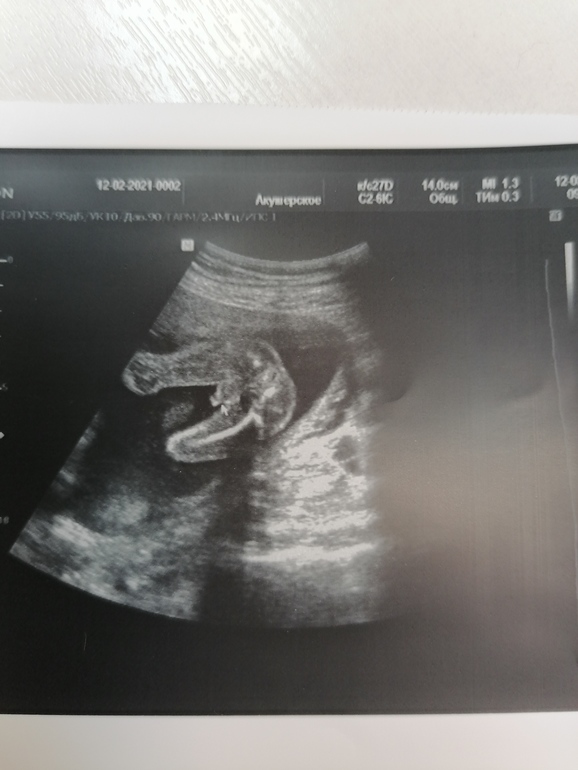

УЗИ прошло шикарно, врач меня вспомнила, все расспросила как и что. Всё рассмотрела идеально. Муж сидел с открытым ртом. Сделали нам аж 15 фото, прям фотосессия была у сыночка🥰😉. Он так мило зевал, язычком водичку ловил💙💙💙. Прям умиление сплошное🥰. Лежит головой вниз.

По УЗИ все отлично, только вот по узи животик в четверг был больше чем сегодня, но это погрешности узи🙈😂. Вес 400гр.

Ну и наши фоточки🥰👶🙏🙏🙏.

Ну и фотосессия сыночка👶🙏🙏🙏🥰.